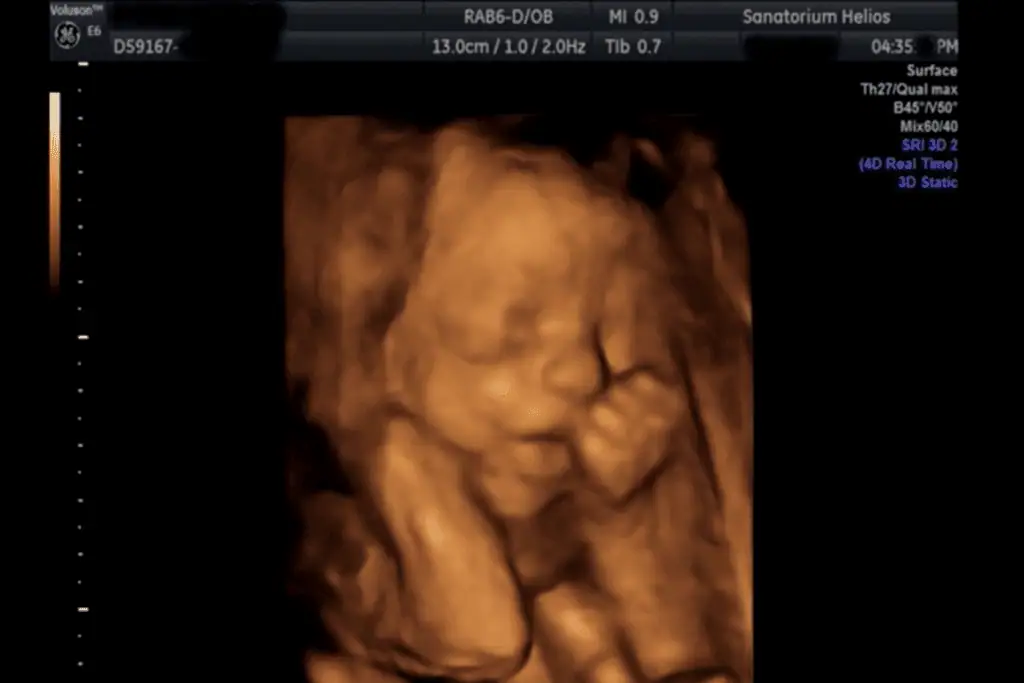

3D, 4D Ultrazvuk

Jako třetí pracoviště v České republice a jako první privátní zařízení mělo Sanatorium Helios k dispozici trojrozměrný ultrazvuk GE Voluson 730. Nově je možné také vyšetření na nejmodernějším přístroji Voluson E10.

Nejvhodnější je záznam plodu mezi 20. – 26. týdnem těhotenství.

Kvalita záznamu na 3D/4D je vždy ovlivněna polohou plodu a polohou placenty, množstvím plodové vody a konstitucí pacientky. Pokud je např. plod přitisknut k děložní stěně nebo k placentě ev. má před obličejem ruce nebo nohy, je zobrazení na 3D velmi nepřesné a mnohdy nejdou kontury tváře vůbec zobrazit.

Ze 3D a 4D ultrazvukového vyšetření lze pořídit fotografii či DVD záznam.

Tyto fotografie jsou pořízené přístrojem Voluson 730